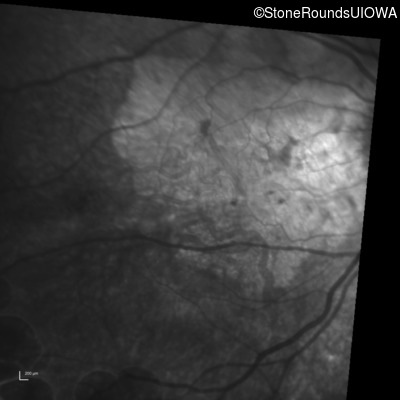

Infrared Fundus Photograph - Right - 20/25 -2

Exemplar